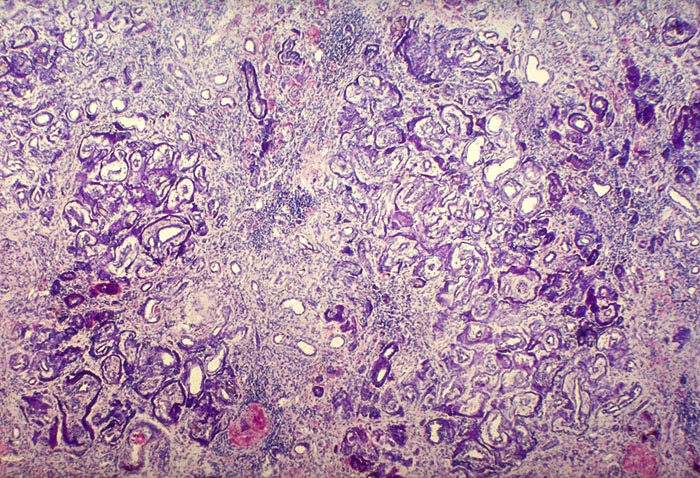

AP/ Nephrokalzinose

Nephrokalzinose

Niere